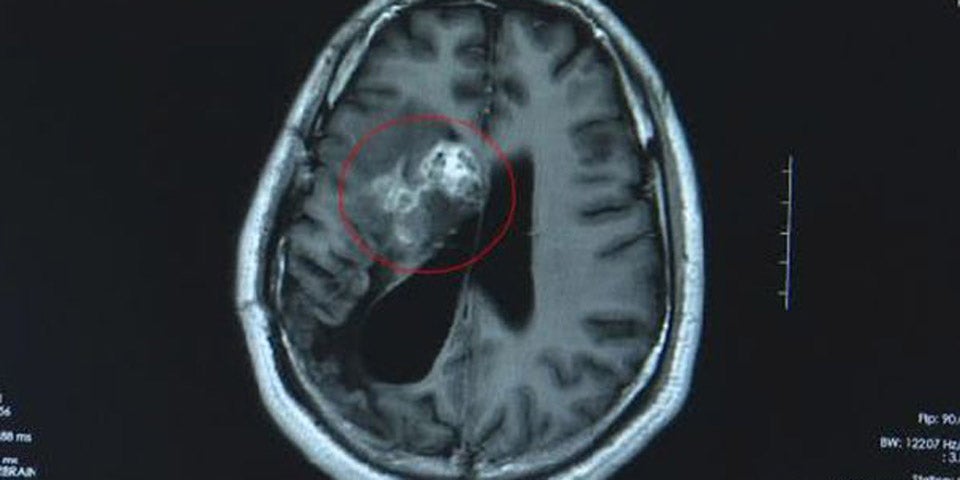

Während einer Operation wurde Wang Lei ein 13 Zentimeter langer, noch lebender Bandwurm aus dem Gehirn entfernt – Dieser soll ganze 15 Jahre lang am Gehirn des Mannes gefressen haben.

China. Bei einer zweistündigen Operation im "Guangdong Sanjiu Brain Hospital" in China entfernten Chirurgen einen 13 Zentimeter langen Bandwurm aus Wang Lei's Gehirn. Der Chinese wurde im Jahr 2007 aufgrund eines linksseitigen Taubheitsgefühl mit einem Hirntumor diagnostiziert. Erst 2018 fanden Ärzte den Ursprung der Symptome: ein Bandwurm, der sich über 15 Jahre im Gehirn des Mannes befand. Da der Wurm in einem sehr sensiblen Areal des Gehirnes entdeckt wurde, versuchten die behandelnden Ärzte den Parasiten mithilfe nicht invasiver Methoden zu entfernen. Unglücklicherweise fraß sich der Wurm immer weiter in das Gehirn von Wang Lei, sodass eine Operation unumgänglich wurde.